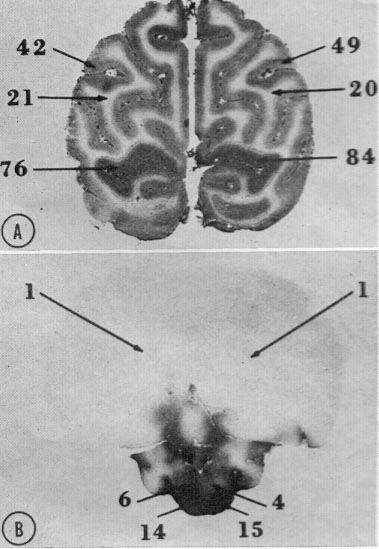

Fig. 7.  Autoradiograph of coronal brain section of normal newborn monkey.   Just prior to being killed,

this animal sustained an intravenous infusion of 14C-labeled antipyrine. Staining density relates to

volume flow of blood per unit of tissue per unit of time. The central nuclei of the inferior colliculi stand out

due to their high-volume blood flow. (Courtesy C. Kennedy and L. Sokoloff, Laboratory of Cerebral

Metabolism, National Institute of Mental Health.)